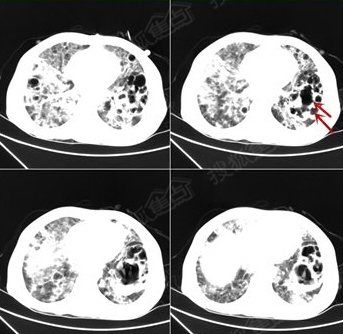

肺部ct显示肺部已经被"腐蚀"出一个个空洞(如箭头所示)

图片尺寸343x334